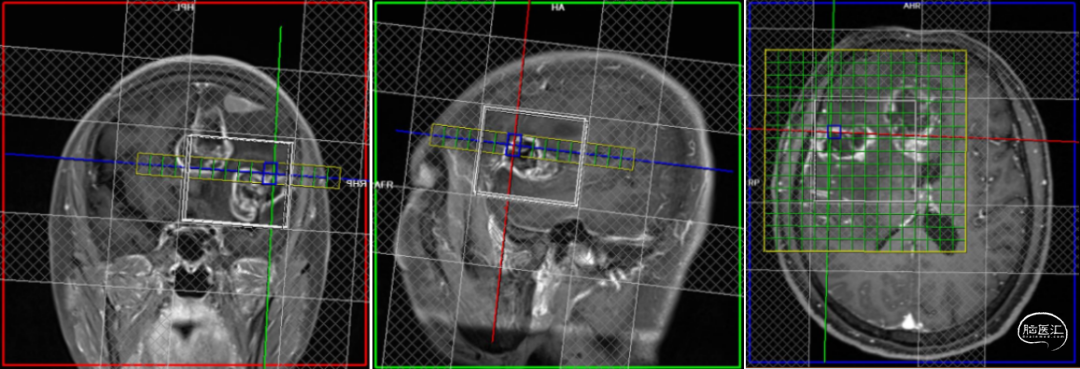

2020-02-12 MRI:双额叶大脑镰旁、胼胝体,右侧颞叶见两个不规则团片状异常信号影,病灶局部形成囊实性肿块,大小分别约3.9×4.6cm及4.0×3.2cm,实性部分T1WI呈等信号,T2WI呈稍高信号,FLAIR呈高信号,高b值DWI呈稍高信号,相应ADC呈低信号,边缘见少许斑点状及条索状T1WI高信号影,增强扫描呈不规则环形强化,病灶周围见大片状水肿,右侧侧脑室前角、体部、后角明显受压,中线结构左偏,脑干受压稍向左偏移。DTI序列图像质量欠佳,示病灶实质区FA值明显降低,纤维束中断破坏,水肿区FA值降低,累及胼胝体及右侧内囊纤维。MRS示病灶实质区Cho升高,NAA降低,Cho/NAA明显升高。另见右额凸面一明显均匀强化病灶,宽基底位于凸面硬膜,边界较清,大小约2.3×2.0cm,T1WI呈低信号,T2WI呈稍高信号,FLAIR呈高信号,高b值DWI呈高信号,相应ADC呈等信号,增强扫描明显均匀强化,邻近脑膜增厚强化呈“脑膜尾征”,病灶邻近颅骨骨质增生。检查印象:临床提示颅内占位,颅脑MRI平扫+增强+DWI+DTI+MRS+MRS:双侧额叶大脑镰旁、胼胝体,右侧颞叶占位,考虑脑肿瘤所致,结合MRS,倾向恶性肿瘤,胶质瘤?不除外高级别脑膜来源肿瘤,脑中线结构左偏,脑干受压稍向左偏移。另,右侧额部肿块,考虑脑膜瘤可能性大

2020-02-12术前核磁影像: